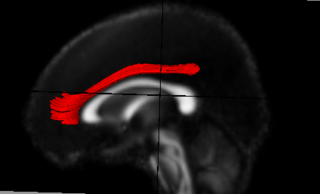

Population tensor atlas with Cingulum bundle tract using b-spline registration